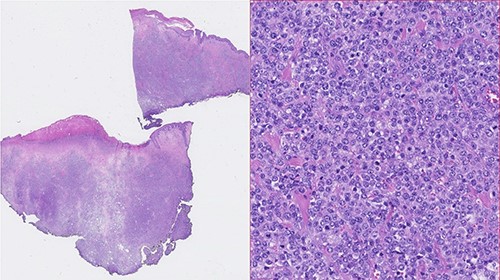

A 73-year-old Caucasian man with a history of hypertension, atrial flutter and Type 2 diabetes mellitus underwent left inguinal hernia repair by Rutkow-Robbins hernioplasty in 2017 without immediate surgical or postoperative complications. In 2021, he reports the appearance of a painless swelling in the left inguinal scar. The patient was medicated with antibiotics without improvement and was sent to the General Surgery consultation with the diagnosis of inguinal mesh rejection. Upon observation by General Surgery, the patient had an ulcerated area of the medial portion of the scar, measuring 1 × 2 cm, with drainage of seropurulent content and surrounding erythema, interpreted as the external orifice of a fistulous tract. The diagnosis of late mesh rejection was maintained, and the patient underwent prosthesis removal without hernia repair. During surgery, extensive peri-mesh fibrosis was found but without apparent signs of infection. The scar was removed en bloc including the ulcerated area and sent for anatomopathological examination. The surgery was uneventful and the patient was discharged. Histological examination (Figs 1–3) revealed extensive involvement of the dermis and hypodermis by a high-grade non-Hodgkin lymphoproliferative process with characteristics of diffuse large-cell B lymphoma, which focally conditions epidermal ulceration. The immunohistochemical study showed diffuse staining for CD20, MUM-1 and CD10, with weak and heterogeneous staining in ~40–50% of neoplastic cells for C-MYC and 80–90% of the same population cell for Ki-67. Immunostains for CD30 were not observed and with anti-CD3 and anti-CD5 antibodies, only marking of scattered rare reactive T lymphocytes was observed. Finally, the neoplastic cell population had no staining for bcl2, but diffuse staining for bcl6. Upon reassessment, the patient had wound dehiscence with an extensive ulcerated area (Fig. 4) and was oriented to hematology. Bone marrow biopsy, myelogram and flow cytometry were normal and computerized tomography of the neck, chest, abdomen and pelvis revealed a right inguinal adenopathy (Fig. 5). The patient was staged as IIa and proposed for systemic treatment with rituximab, cyclophosphamide, doxorubicin, vincristine and prednisolone (R-CHOP).

Photomicrographies. Left: HE ×5, with an area of hypodermic adipose tissue infiltrated by the neoplastic lymphoid population. Center: Immunohistochemical staining of the same area, revealing diffuse expression of CD20 by neoplastic lymphoid cells. Right: Absence of CD3 expression in the neoplastic cell population and expression only in a small amount of dispersed reactive T lymphocytes.